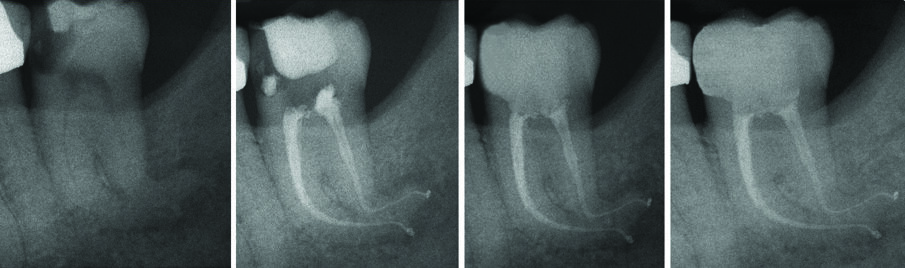

All’esame radiografico le otturazioni appaiono dense ed omogenee, la guttaperca mostra un buon adattamento alla morfologia endodontica, determinando un buon riempimento delle irregolarità del sistema canalare. Sono stati evidenziati la presenza di canali laterali ed uscite apicali multiple. Figg. 8a-8e molare superiore, Figg. 9a-9e molare inferiore, Figg. 10a-10c molare superiore, Figg. 11a-11d anatomie complesse premolare curvo e Figg. 12a-12d ottavo.

Fig. 11 - Terapia canalare 3.8.